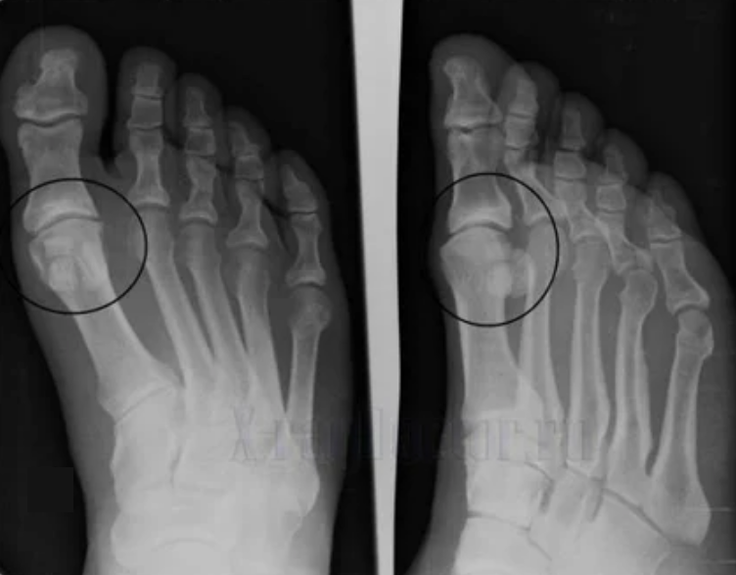

Para fazer um diagnóstico, os reumatologistas estudam as queixas do paciente e prescrevem um exame de raios X. Na maioria das vezes, a radiografia é usada em 2 projeções. O médico analisa a presença de distúrbios distróficos na cartilagem hialina e nas articulações ósseas. Se a lacuna articular for reduzida, os ossos serão deformados ou achatados, existem formações císticas na superfície da cartilagem, os osteófitos são sinais óbvios de artrose. Durante a inspeção, a artrose indica a instabilidade da articulação: o eixo dos membros e subluxação é perturbado.

Muitas vezes, uma imagem de raio X não é capaz de fornecer informações completas sobre a condição da articulação. Para um estudo mais completo, a tomografia computadorizada é prescrita, é eficaz para examinar ossos. A ressonância magnética é mais frequentemente usada para estudar tecidos moles.